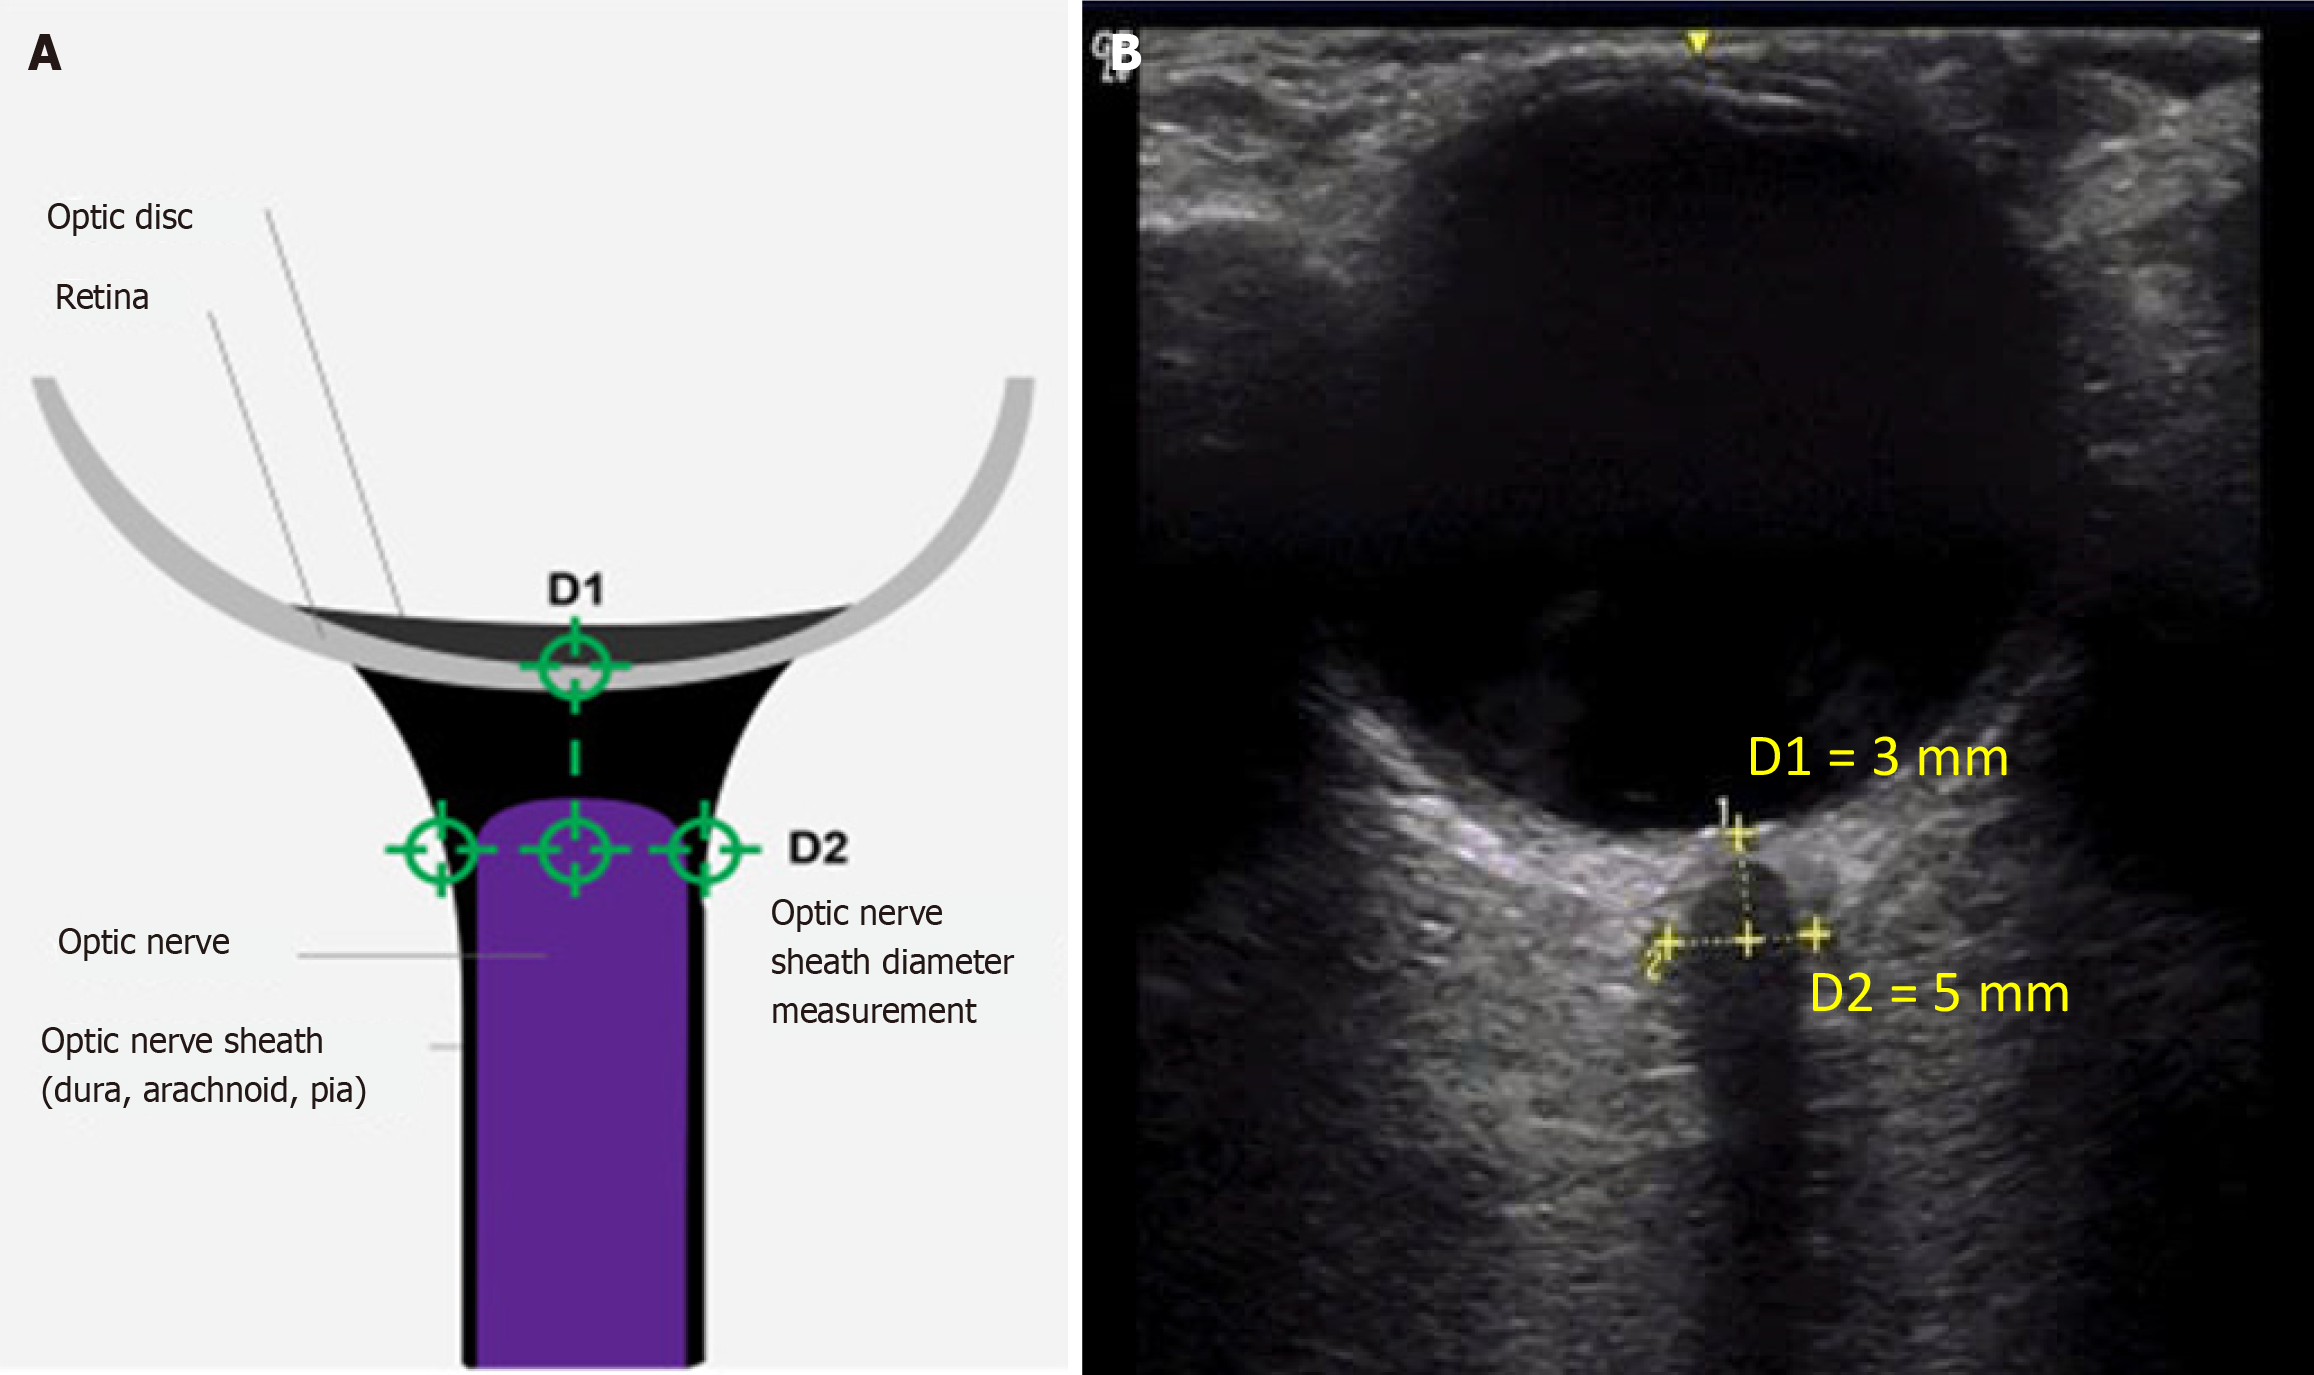

Figure 1 Anatomical landmarks and ultrasonographic measurements of optic nerve sheath diameter.

A: Anatomical landmarks used for optic nerve sheath diameter measurements; B: Enlarged optic nerve sheath on transorbital ultrasonography in a patient with traumatic brain injury. The patient was examined in the supine position with eyes gently closed, and a copious amount of acoustic gel was applied to the upper eyelid to prevent direct pressure on the globe. The probe was positioned lightly over the closed eyelid in the axial plane to visualize the optic nerve posterior to the globe. Two perpendicular diameters of the optic nerve sheath were measured 3 mm posterior to the retina: The vertical diameter (D1 = 3 mm) and the horizontal diameter (D2 = 5 mm). The mean values of D2 were used for further analysis.